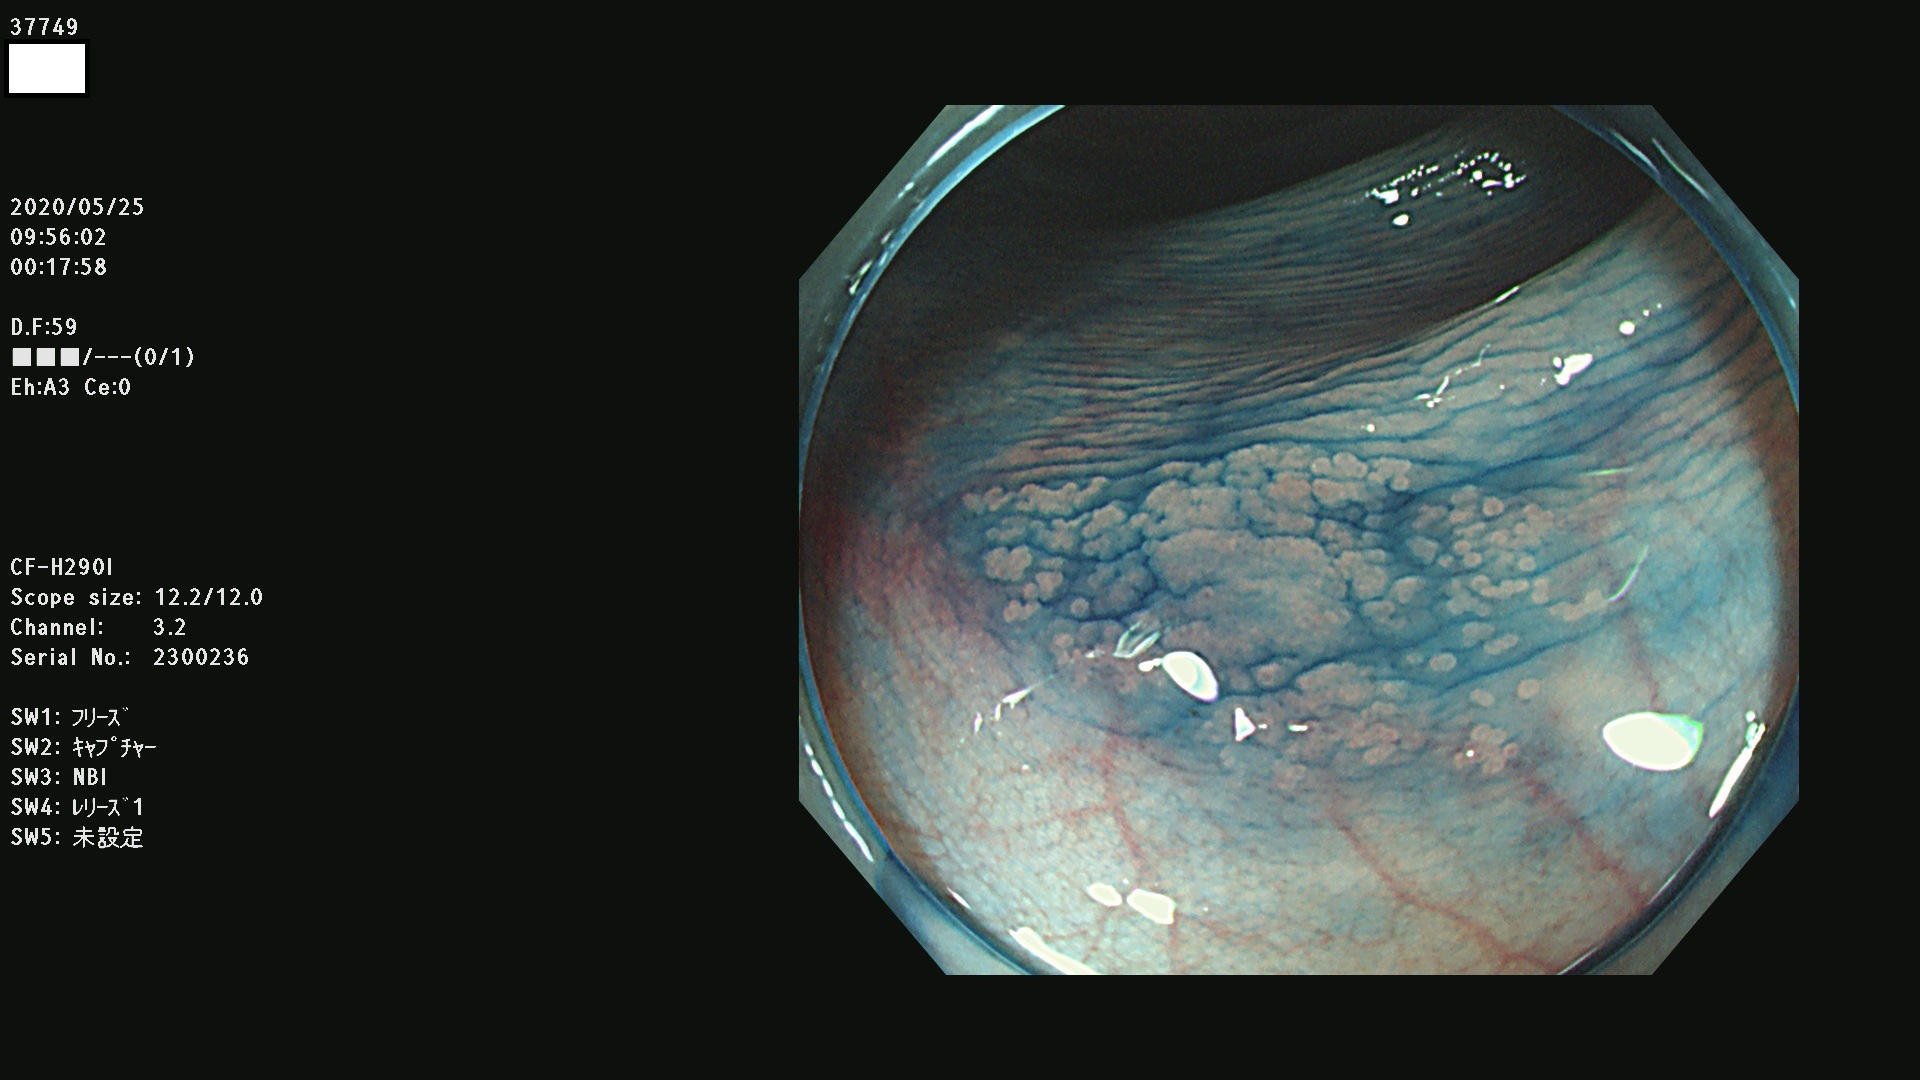

37700 37701 37702 37703 37704 37705 37706 37707(SSAPのみ) 37709 37711 37712 37715 37716 37717 37720 37722(SSAPのみ) 37724 37725 37726 37727 37728 37729 37731 37732 37733 37736(SSAPのみ) 37737 37739 37740 37741 37742 37744 37745 37748 37749 37750 37751 37752(SSAPのみ) 37753 37754 37755 37757 37758 37760 37761 37762(SSAPのみ) 37763 37764 37765 37766 37767 37768 37769 37771 37772 37774 37775 37776 37777 37780 37781 37782 37783 37784 37785 37787(SSAPのみ) 37788 37791 37792 37793 37794 37795 37799

発見困難で危険性の高い平坦型病変(上記100名より抽出)